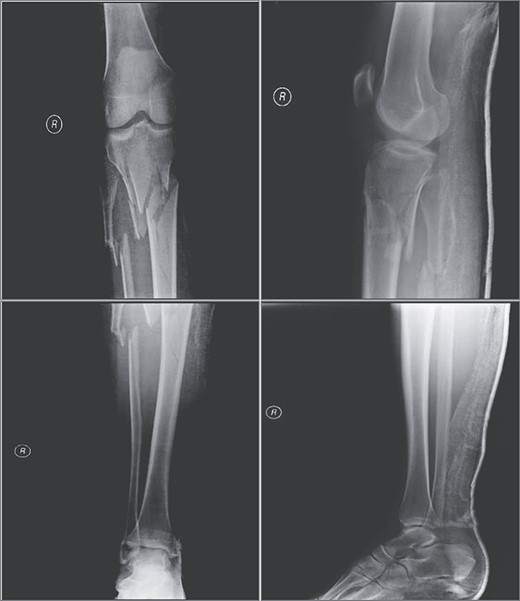

Three weeks after initial injury, minimally invasive osteosynthesis was performed using a 12-hole precontoured proximal lateral tibia plate (I.T.S., GmbH, Graz/Austria). Patient was draped and placed in supine position under spinal anesthesia: nonsterile pneumatic tourniquet was placed and inflated to 350 mmHg. The external fixator was removed, and an anterolateral incision was made on the right proximal tibia for fracture fixation. Insertion guide and plate were inserted between anterior tibialis muscle and periosteum. Insertion of screws was performed with the aid of C-arm fluoroscopy (for proper screw placement). After tourniquet was deflated, surgical incision was closed with sutures. During the procedure, no signs of brisk bleeding or damage to neurovascular structures were observed. Immediately after the procedure, the patient exhibited symmetrical palpable peripheral pulses of dorsalis pedis and posterior tibialis arteries. Postsurgical radiographic images revealed excellent fracture reduction and alignment (Fig. 2). Hospital stay was uneventful, and patient was discharged home the next day with pertinent postoperative management instructions.

(A) Anteroposterior and (B) lateral views of the right tibia following minimally invasive percutaneous osteosynthesis. Images reveal proper alignment and fracture reduction.